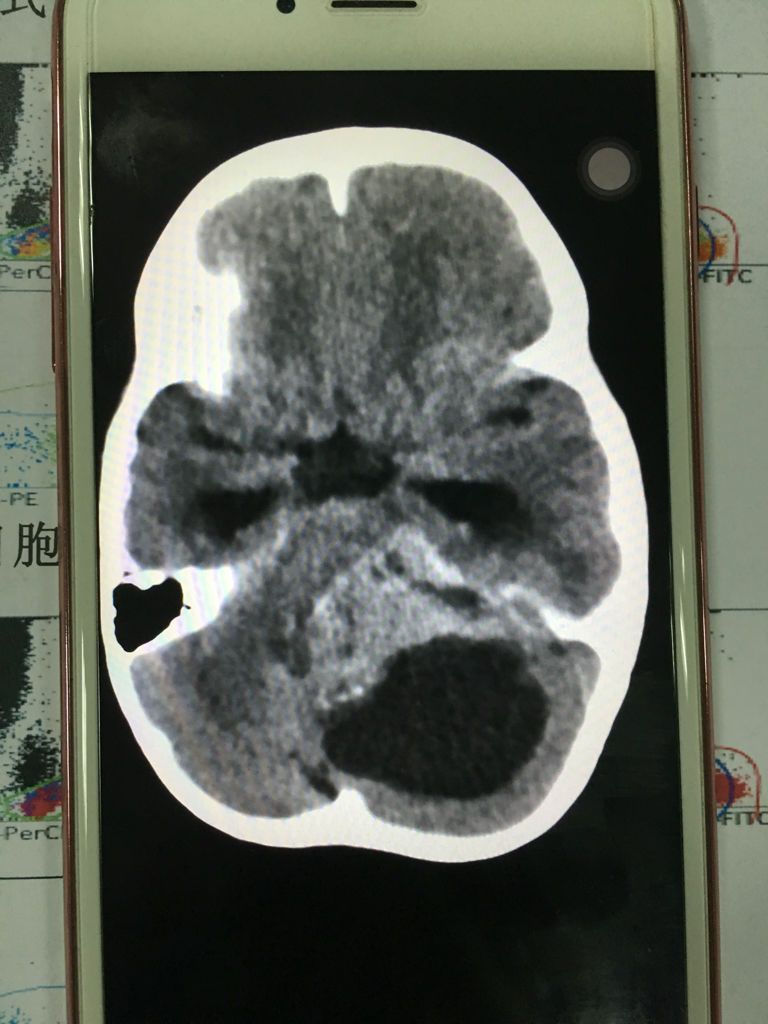

你所说的水母细胞瘤应该是:髓母细胞瘤,它是一种好发于儿童的颅内恶性肿瘤,是中枢神经系统恶性程度最高的神经上皮性肿瘤之一,主要表怪细现为颅内压增高和共济失调等小脑症状常有点堡复视及多种脑神经障碍。医生的孟毯玻意见主要是手术切除与术后放射治疗,部分病例可辅以化疗。